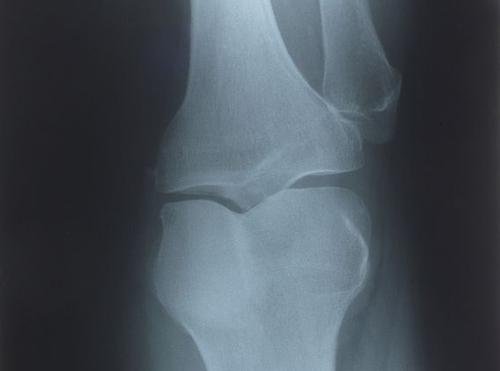

一位35歲的男子,平時喜愛戶外運動,今年農曆年前和機車擦撞,造成左膝關節前側有撕裂傷,傷口癒合良好。康復後便再次騎腳踏車運動,隔天早上卻發現左膝關節腫脹無法行走,進一步檢查才發現,受傷時導致膝關節的後十字韌帶斷裂及半月板破裂,但X光未檢查出。澄清醫院中港院區骨科主治醫師黃泰榮表示,這類受傷第一時間X光難檢測出來,最好在關節腫脹消退後,再做一次詳細檢查,確保傷口真正痊癒。

黃泰榮透露,患者就醫時發現膝關節有積液和關節不穩定情形,透過核磁共振檢查後,發現膝關節的後十字韌帶斷裂和半月板破裂。患者對於未在第一時間發現這個問題,感到非常不諒解。但黃泰榮解釋,膝關節韌帶斷裂及半月板破裂,第一時間難用X光檢查出來,隨著撕裂傷口縫合後,若復原期間沒有運用膝關節,就不會有明顯性的疼痛,但後來開始運用到膝關節,損傷的韌帶和半月板立即惡化發炎,便造成患者無法行走。